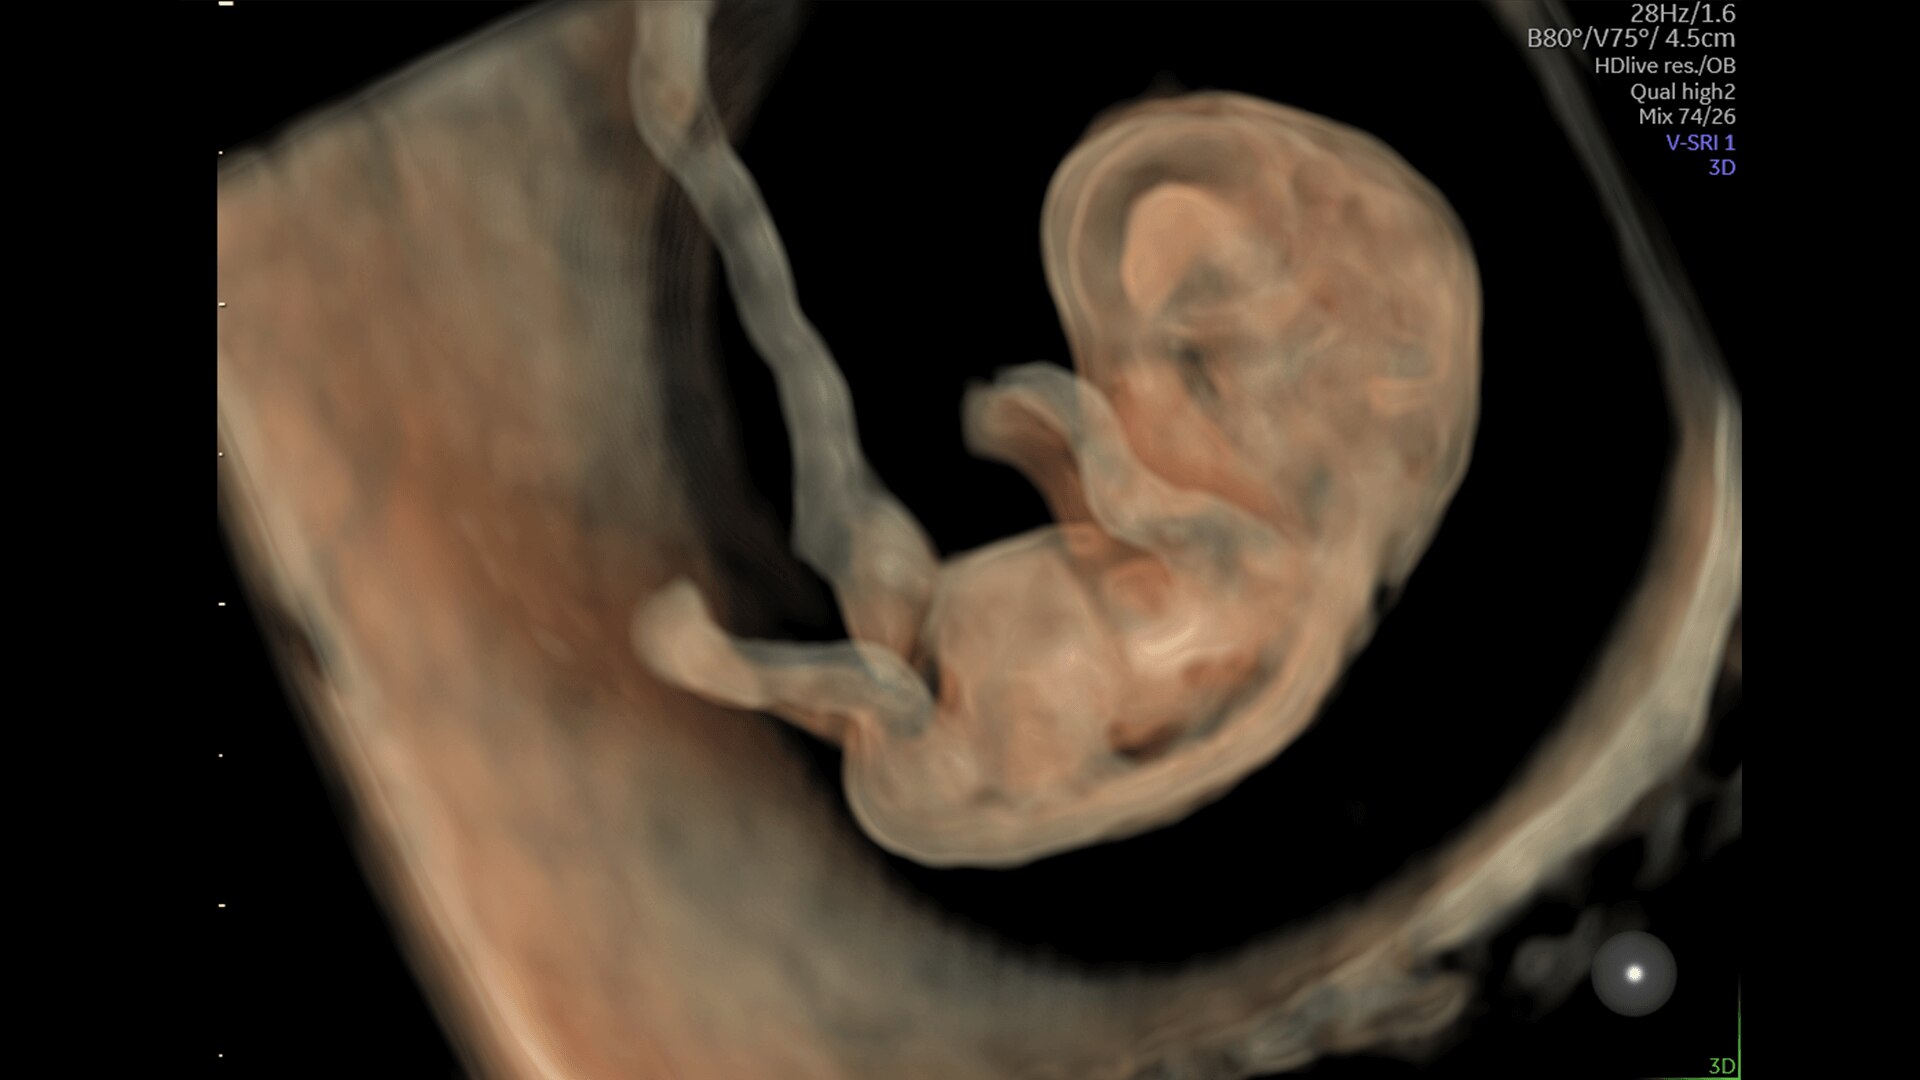

Complex cases come with enough uncertainty. That's why the Voluson Expert 22 is specifically designed for in-depth assessment of complicated anatomy — with pioneering first trimester, fetal cardiac, gynecological, and other pivotal technologies that focus on early detection and intervention.

First Trimester Exams

Perform detailed exams with high-resolution for early insights to fetal health